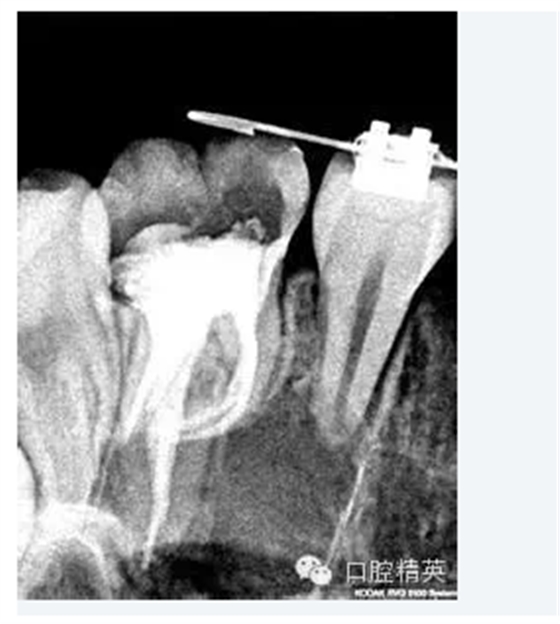

5.根管髓腔部分的預(yù)先擴(kuò)大可以幫助牙醫(yī)做出更明確的診斷。預(yù)先擴(kuò)大的根管髓腔部分可以容納較大型號(hào)的金屬根管擴(kuò)大器,X光片顯示更清晰;由于接觸頭更容易的與髓腔牙本質(zhì)接觸,電子根尖定位器的顯示也更明確。

當(dāng)根管的髓腔向2/3的擴(kuò)大完成以后,臨床牙醫(yī)即可順利的進(jìn)行根尖1/3的擴(kuò)大及最后精細(xì)完成。因?yàn)榇蟛糠值难栏鶑澢胺植娑及l(fā)生在該區(qū)域,所以,應(yīng)先應(yīng)用小型的不銹鋼可彎曲的根管擴(kuò)大針對(duì)其進(jìn)行小心而精密的探測(cè),以獲得更詳細(xì)而準(zhǔn)確的診斷資料。

2.確定根尖孔的合適開(kāi)放根據(jù)X線片(RT)確定的根尖孔位置,將一柔軟的10號(hào)擴(kuò)孔銼輕輕推進(jìn)。為了保證根尖孔的良好開(kāi)放,應(yīng)保證擴(kuò)孔銼尖端超過(guò)根尖孔1mm, 同時(shí)減少齲壞牙本質(zhì)碎霄的堆積 (在10號(hào)擴(kuò)孔銼其D1位置的直徑為0.12mm) ,輕輕的將之向前推進(jìn)1mm,以提供更大的空間,保證所有牙髓組織碎片、齲壞牙本質(zhì)碎霄的清除及沖洗液的自如進(jìn)出,同時(shí)降低根管堵塞的發(fā)生率。根尖孔完全開(kāi)放或10號(hào)擴(kuò)孔銼向前推進(jìn)幅度不足1mm都是不可取的,因?yàn)榕R床研究表明:兩種選擇的治療結(jié)果都不甚理想。